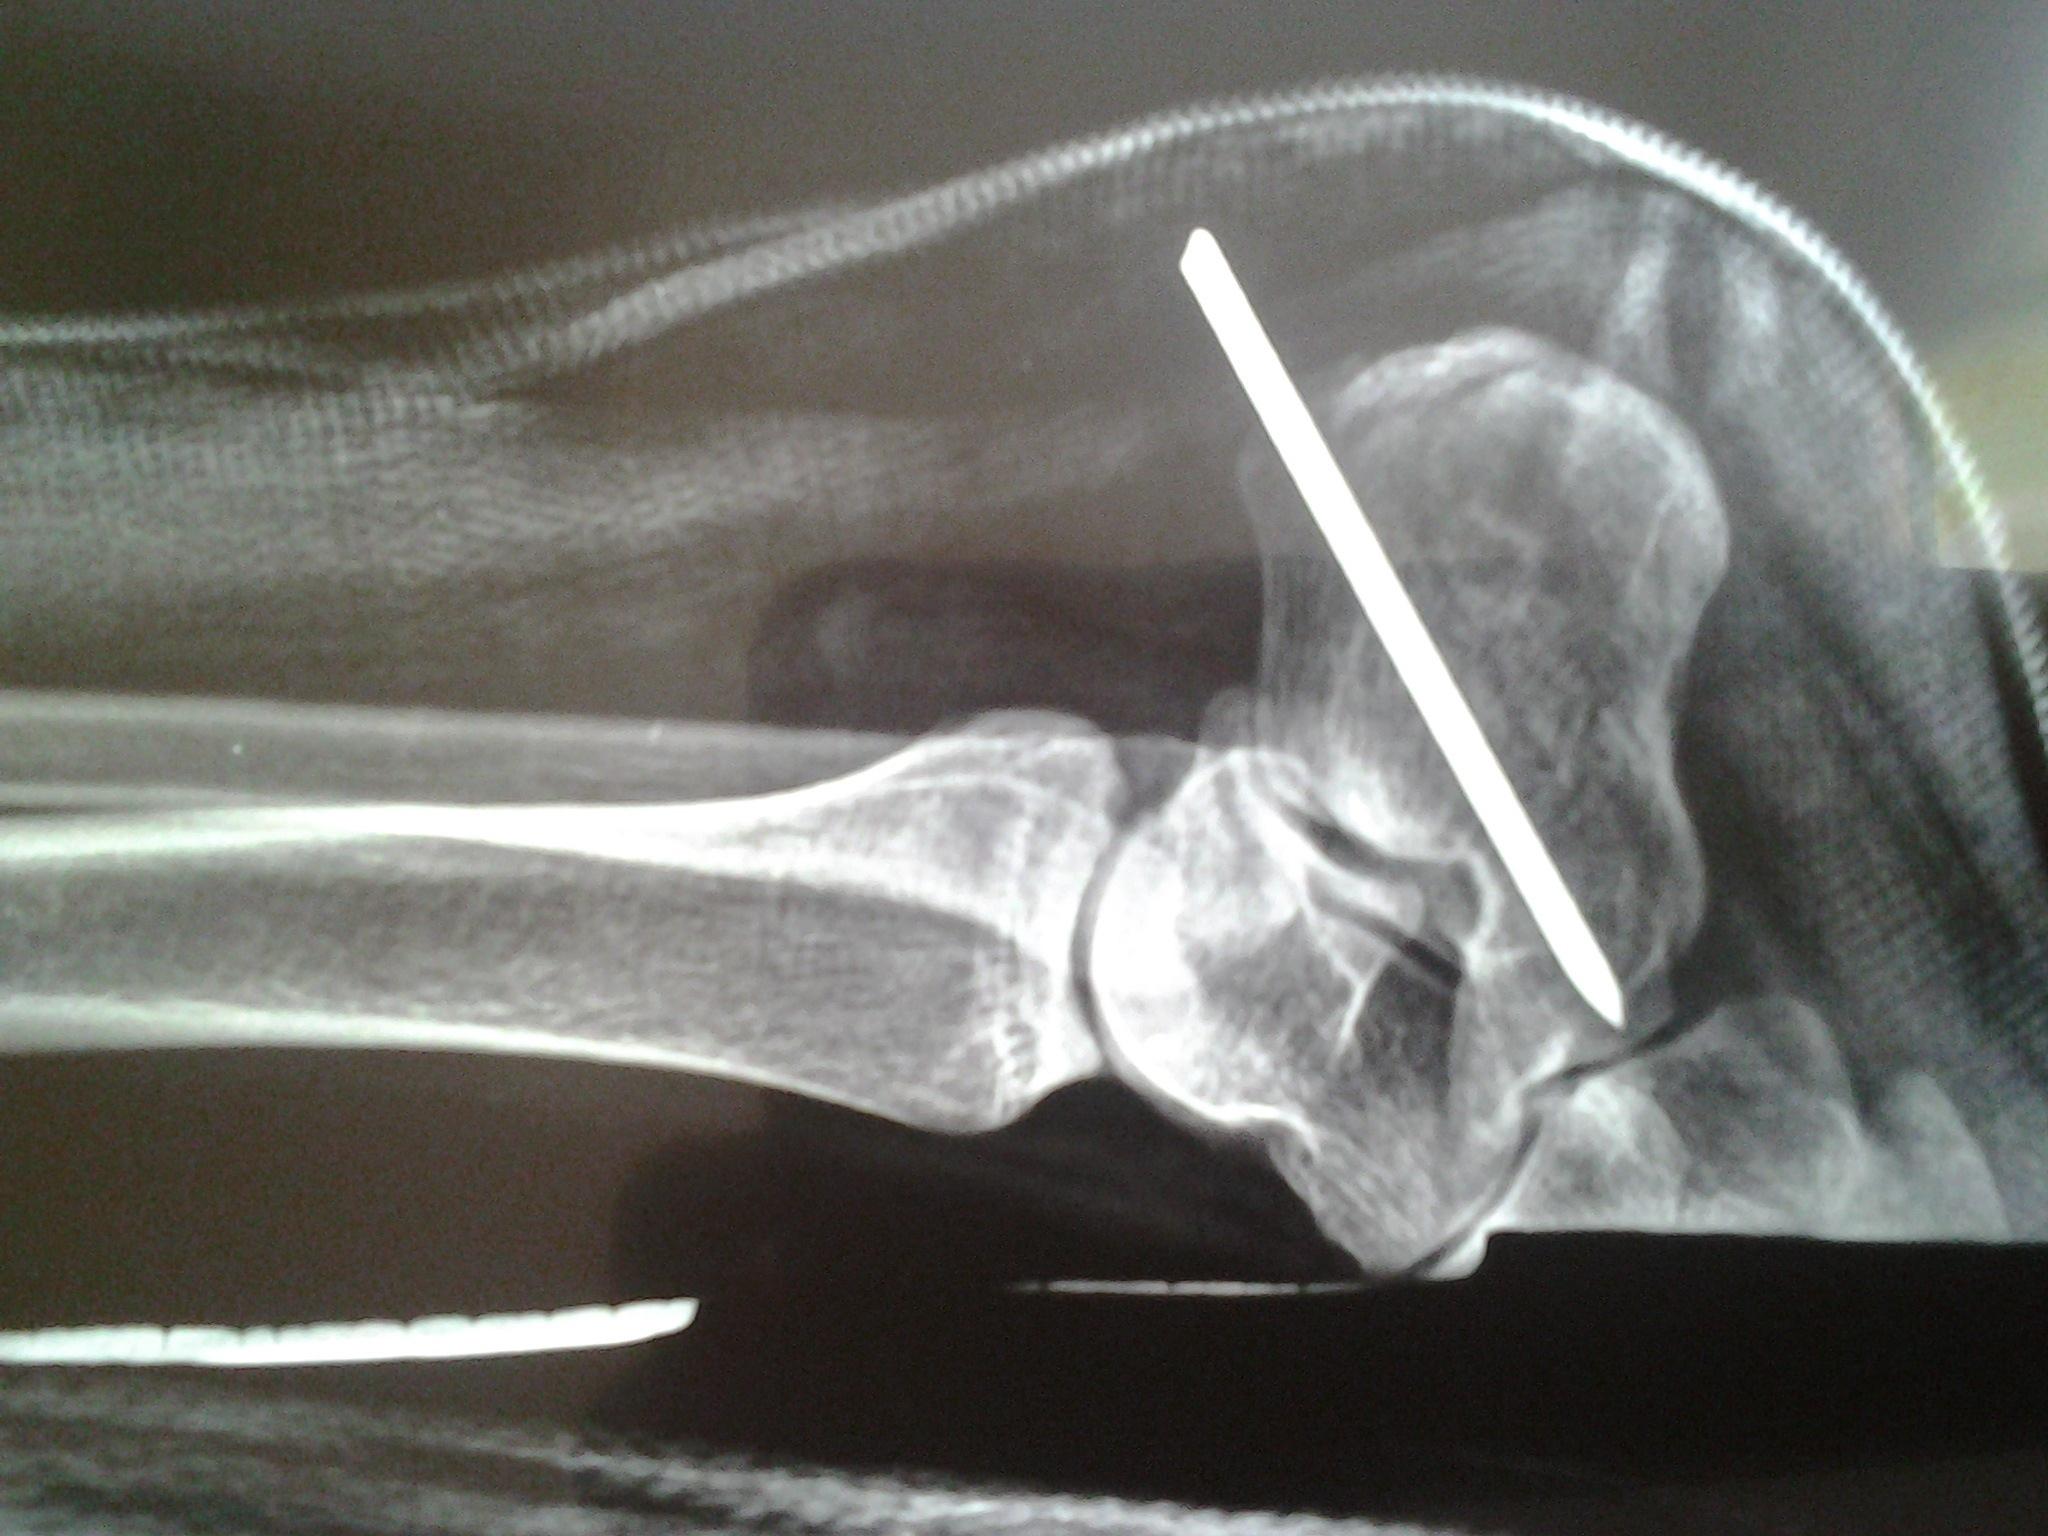

根骨骨折的片子 这是怎么情况 根骨粉碎了吗?